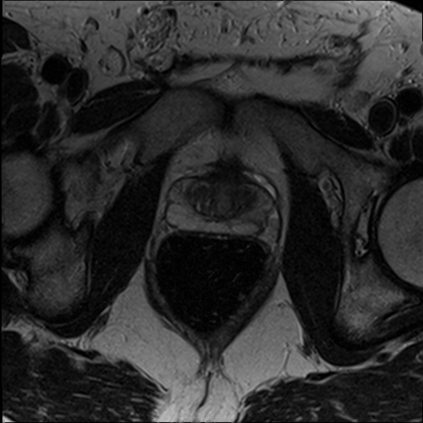

The Conditional Random Field as a Recurrent Neural Network layer is a recently proposed algorithm meant to be placed on top of an existing Fully-Convolutional Neural Network to improve the quality of semantic segmentation. In this paper, we test whether this algorithm, which was shown to improve semantic segmentation for 2D RGB images, is able to improve segmentation quality for 3D multi-modal medical images. We developed an implementation of the algorithm which works for any number of spatial dimensions, input/output image channels, and reference image channels. As far as we know this is the first publicly available implementation of this sort. We tested the algorithm with two distinct 3D medical imaging datasets, we concluded that the performance differences observed were not statistically significant. Finally, in the discussion section of the paper, we go into the reasons as to why this technique transfers poorly from natural images to medical images.